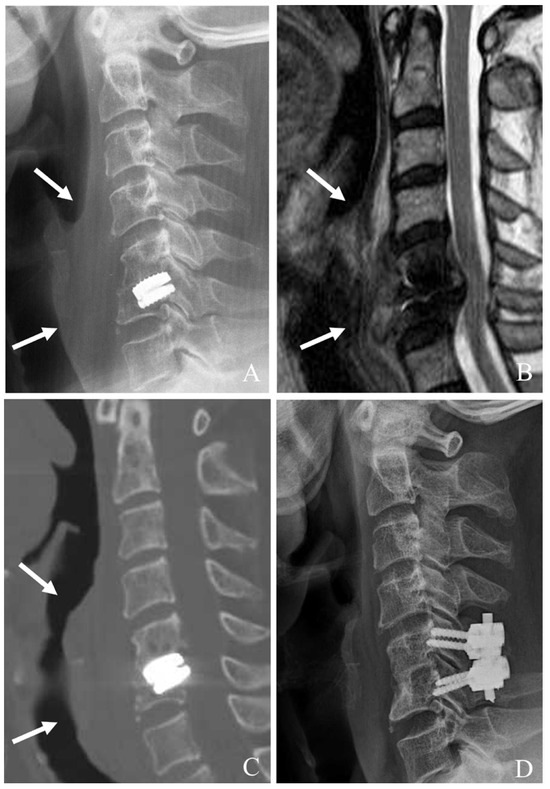

For ACDF, after device removal, the intervertebral space is prepared for fusion. A structural graft (autograft, allograft, or synthetic cage) is placed, followed by anterior plating to provide immediate stability. In cases of severe bone loss or multilevel involvement, a corpectomy may be required, with the placement of a cage or graft to restore anterior column support for ACCF (Figure 2). The decision between two-level ACCF and three-level ACDF must be individualized based on the patient’s pathology, bone quality, and sagittal alignment needs. While corpectomy provides better deformity correction, it carries higher surgical risk and requires more extensive stabilization. In contrast, three-level ACDF is less invasive but has higher rates of pseudarthrosis, potentially leading to revision surgery. Understanding these nuances allows for more tailored surgical planning and improved patient outcomes [31,32].

Figure 2. Plain X-rays (A), computed tomography (B), and magnetic resonance image (C) showing cervical disc arthroplasty at C5–6 and ossification of the posterior longitudinal ligament (OPLL) of C6 body (white arrow) causing cord compression. The patient underwent removal of the C5–6 prosthesis and OPLL and anterior cervical corpectomy and fusion (D).